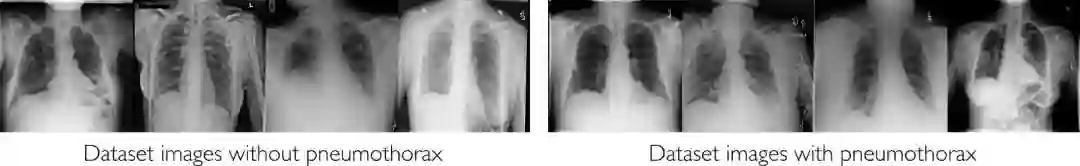

第二个 lab 补充了课程中用于计算机视觉的深度学习一节。学生有机会在逼真的医疗图像数据集上使用 CNN 检测疾病。特别地,学生使用一组真实的胸部 X 射线构建模型,检测和分类被预测有气胸的扫描,这种情况发生在肺与胸壁之间的空气量异常的情况下。

数据集

在这里,我们使用了 ChestXRay 数据集的一个子集。顾名思义,这是一个大型 X 射线胸透照片数据集,并标有相应的诊断信息。

鉴于它是一个基于真实世界信息的数据集,其中含有大量噪音。在这里,我们希望让学生们能够使用真实的数据,以便了解包装和注释数据会面临的挑战——特别是在计算机视觉的背景下。